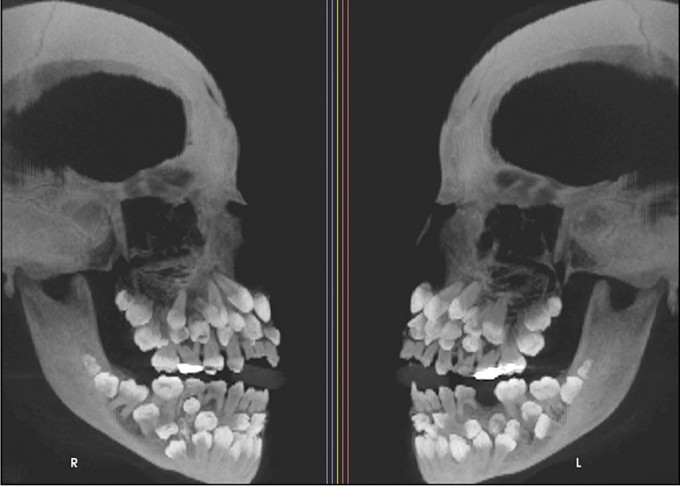

Cụ thể, bé gái 11 tuổi 8 tháng ở Minas Gerais, Brazil, đã đến một phòng khám nha khoa để kiểm tra răng miệng và dự định nhổ hàng răng sữa trên cùng vốn vẫn chưa rụng. Tuy nhiên, kết quả chụp X-quang cho thấy một phát hiện gây sốc, thực tế bé có 18 răng sữa, 32 răng vĩnh viễn và 31 răng thừa, tổng cộng là 81 răng.

Bé gái có 81 chiếc răng khiến nha sĩ bất ngờ.

Khi khám răng, bác sĩ nhận thấy chỉ có 5 răng vĩnh viễn đã mọc, trong khi vẫn còn khá nhiều răng sữa. Để đánh giá toàn diện hơn tình trạng răng miệng của bé, bác sĩ đã chỉ định chụp X-quang tổng quát và chụp sọ nghiêng.

Những hình ảnh cho thấy nhiều răng bị biến dạng và nằm sâu trong nướu, khiến việc phân biệt giữa răng bình thường và răng thừa rất khó khăn. Trung bình, một người trưởng thành có 32 chiếc răng và những chiếc răng thừa này được gọi là "siêu răng". Thông thường, chỉ có 1 hoặc 2 chiếc răng thừa.